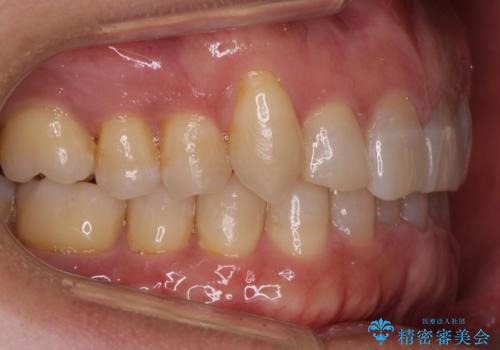

八重歯と下の歯のがたつき マウスピースで

- 右上の犬歯が目立つのが気になる、下の歯並びも治したいとのことで来院。

歯を抜かずに少し削って小さくして並べました。

並びも良くなり、患者様にも喜んでいただきました。

右上の犬歯の歯肉退縮自体は進行する可能性をお伝えしておりましたが、特に変化なく治療できました。

歯肉退縮につきましては、歯ぐきの移植を提案しましたが特に希望されませんでした。